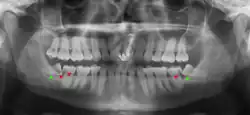

Impacted wisdom teeth are classified by their direction of impaction, their depth compared to the biting surface of adjacent teeth and the amount of the tooth's crown that extends through gum tissue or bone. Impacted wisdom teeth can also be classified by the presence or absence of symptoms and disease. Screening for the presence of wisdom teeth often begins in late adolescence when a partially developed tooth may become impacted. Screening commonly includes a clinical examination as well as x-rays such as panoramic radiographs.

There is no standard to screen for wisdom teeth. It has been suggested, absent evidence to support routinely retaining or removing wisdom teeth, that evaluation with panoramic radiograph, starting between the ages of 16 and 25 be completed every 3 years. Once there is the possibility of the teeth developing disease, then a discussion about the operative risks versus long-term risk of retention with an oral and maxillofacial surgeon or other clinician trained to evaluate wisdom teeth is recommended. These recommendations are based on expert opinion level evidence.[19] Screening at a younger age may be required if the second molars (the "12-year molars") fail to erupt as ectopic positioning of the wisdom teeth can prevent their eruption. Radiographs can be avoided if the majority of the tooth is visible in the mouth.